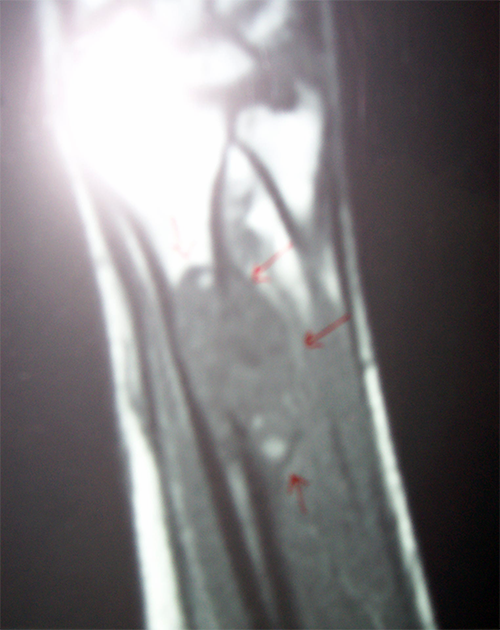

MRI-AP View

Trauma Surgeon in Ahmedabad|Joint Replacement

MRI